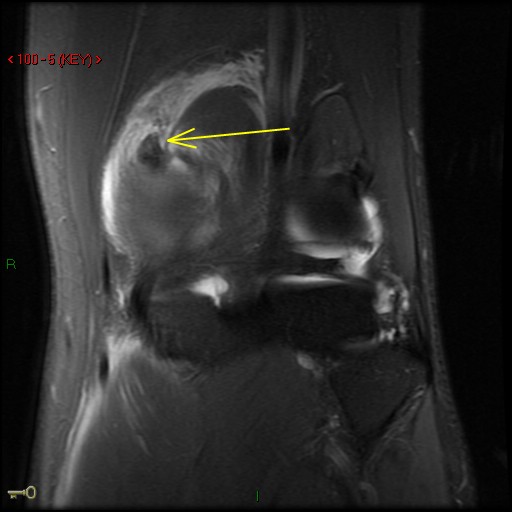

Figure 2 for case Medial head of gastrocnemius muscle ( RID2921 ) avulsion

Figure 2